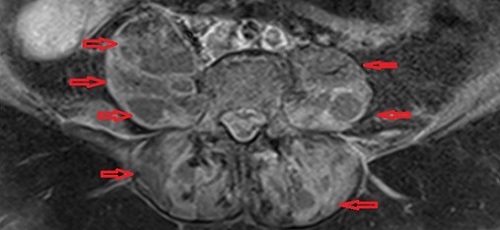

Στις εικόνες της μαγνητικής διακρίνονται τα διάφορα αποστήματα (κόκκινα βέλη) στους μύες (λαγνοψωίτες, απιοειδείς και δεξιό γλουτιαίο).

Το απόστημα του δεξιού λαγονοψωίτη καταλάμβανε ολόκληρη την έκταση του μυός. Τέλος, σημαντικό νέο εύρημα ήταν η παρουσία επισκληρίδιου εμπυήματος το οποίο κρίθηκε ότι δεν χρειάζεται χειρουργείο.